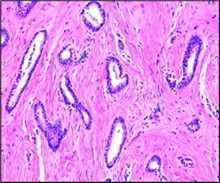

Figure 1.Tubular carcinoma delineating tubules layered by cuboidal to columnar epithelial cells impregnated with miniature to intermediate nuclei, apical snouts and surrounding desmoplastic stroma 7.

Figure 2.Tubular carcinoma delineating cords and cellular tubules lined by cuboidal to columnar epithelial cells imbued with miniature to intermediate nuclei, apical snouts and surrounding desmoplastic stroma 8.

Upon microscopy, invasive tubular carcinoma breast configures as a grade I neoplasm and expounds an infiltrative pattern of tumour evolution. Frequently, invasion of tumour cells into circumscribing adipose tissue and fibrous tissue stroma may ensue or a desmoplastic stromal response may be evoked3, 4.

Around > 90% of tumefaction is comprised of miniature, ovoid or angulated tubules demonstrating open lumens. Neoplastic tubules are coated by singular layer of cuboidal to columnar epithelial cells impregnated with uniform, miniature to intermediate, low grade nuclei. Frequently, tumour cells display apical cytoplasmic tufts or snouts. Intraluminal secretion or calcification may be discerned. Neoplastic tubules appear devoid of encompassing myoepithelial cells.

Mitotic activity is minimal. Neoplasm is devoid of significant cytological atypia, multi-layering or enhanced mitotic activity 3, 4. Neoplastic cells appear immune reactive to oestrogen receptors (ER) and immune non reactive to HER2.